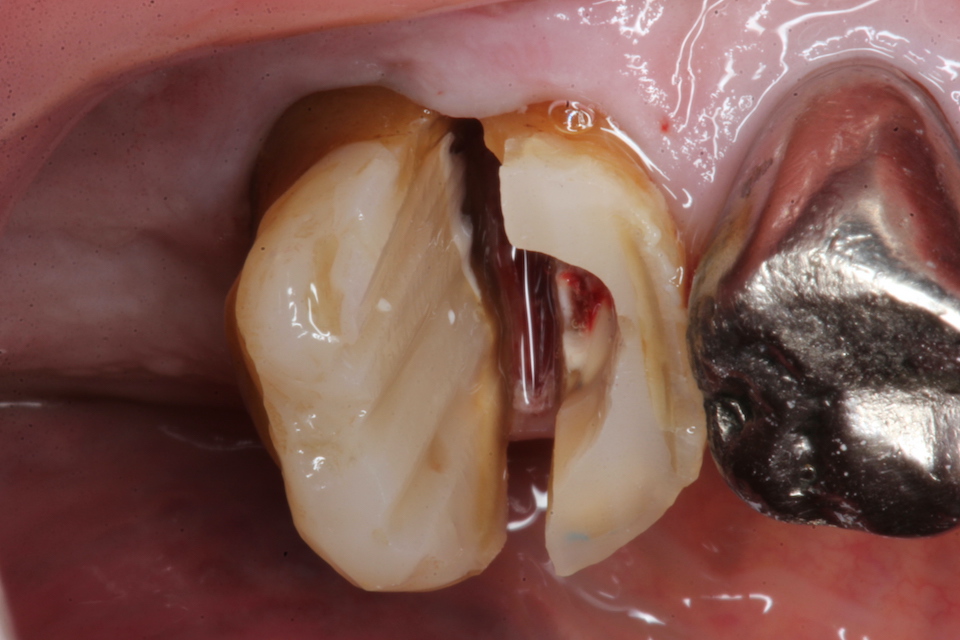

今日の抜歯再植術シリーズ39.1 2025.11.14

今日の抜歯再植術シリーズ39.0 2025.11.13

今日の抜歯再植術シリーズ38.3 2025.10.14